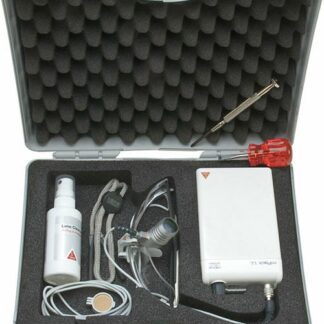

Aprašymas

Išilginis pjūvis – kelio modelis – Erler Zimmer

Priekinis išilginis žmogaus kelio sąnario pjūvis. Kaulų struktūra, meniskai, sąnarių kremzlės, sinovinė membrana ir sąnarių raiščiai pavaizduoti spalvotai. Natūralaus dydžio.

Dydis: 19 x 8 x 4 cm

Svoris: 0,3 kg